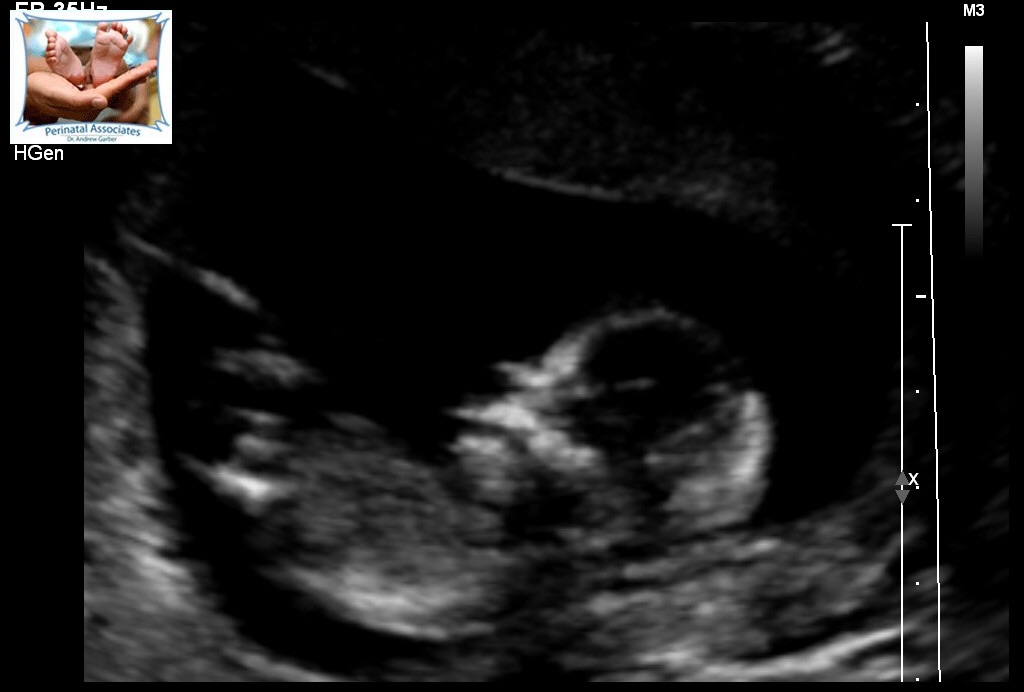

This is from 13 weeks. Can anyone guess what gender? The tech could not find a penis or nub like thing (looked for 30 minutes) and determined she is not convinced about it being a boy but could not exactly see the girl parts.Attachment 26141Attachment 26142Attachment 26143Attachment 26144